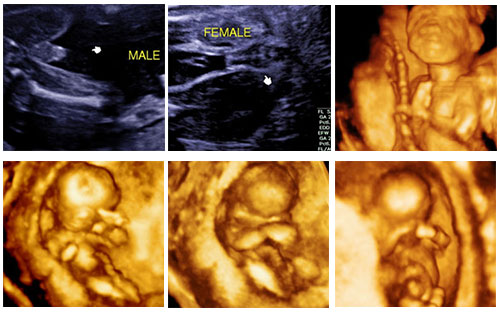

- มีเครื่องอัลตราซาวด์ 4 มิติ ที่สามารถตรวจดูลูกน้อยได้ชัดเจนขึ้น สามารถดูต่อเนื่องเป็นภาพเคลื่อนไหวได้ ซึ่งจะช่วยให้แพทย์ได้ข้อมูลที่แม่นยำขึ้นและเพิ่มประสิทธิภาพในการแปลผลชัดเจนขึ้น

- การตรวจประเมินภาวะของทารกในครรภ์

- การวินิจฉัยด้วยเครื่องอัลตราซาวด์